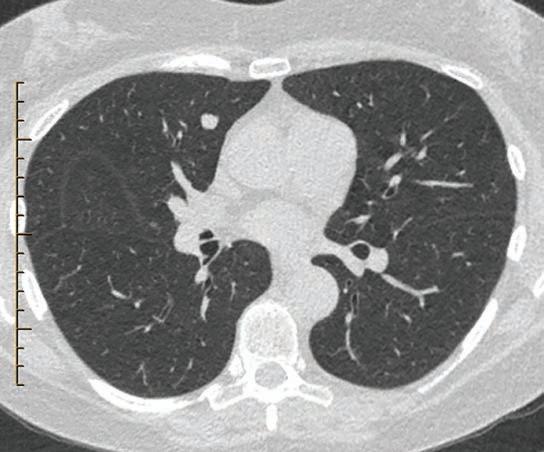

Every few decades a revolutionary discovery is made that changes the outcome of a chronic disease for millions of sufferers. Now, based on the results emerging from researchers at Perth’s Harry Perkins Institute, one such revolutionary breakthrough in the treatment of peripheral artery disease is about to be realised in WA.

Medical Forum spoke with the Perkins Institute’s Associate Professor Juliana Hamzah and vascular surgeon and Head of Department of Vascular and Endovascular Surgery at Sir Charles Gairdner Hospital Professor Shirley Jansen, about what could be the biggest advance in the treatment of atherosclerosis since the invention of statins at the end of the 1970s – and one that potentially dwarfs them –the very real chance of a cure.

“The amazing development we would like to share is that we think we might have a drug that can fix this problem,” Professor Hamzah said. “We actually designed this drug initially for treating cancer. We know that it can work in cancer by improving blood vessel circulation to increase drug uptake by tumours.

“We stumbled upon this while investigating a drug for older cancer patients with cardiovascular

comorbidities as cancer drugs nearly always cause cardiovascular issues. It was intended that we could give this drug in combination with cancer therapy to high-risk patients to improve safety and efficacy.

“And that's where Shirley and I have teamed up for the past 10 years. Our goal was to reduce the risk of vascular events, prevent amputation and reduce hospitalisation.

“Amputation is a major problem –some people would rather die than lose a leg. Australia has the second highest amputation rate in the developed world after the US.”

The past few years have seen the widening of the armamentarium of interventionalists from simple angioplasty, stenting, thrombolysis and open bypass grafting to endovascular devices such as atherectomy, laser, cryotherapy, ultrasonic ‘shockwave,’ drugcoated balloons and stents, and absorbable scaffolds.

However, although existing antithrombotic therapies can lower cardiovascular risk, their net effectiveness can be limited by bleeding complications, and while lipid-lowering medications such as statins are strongly recommended in global guidelines, they do not actually remove the build-up of plaque from the arteries.

“All have their advantages and limitations from not only the technology itself and its applicability but also the heterogenous nature of PAD lesion location, length, and calcium load,” Professor Jansen said.

“Similarly, all these invasive treatments are not curative but merely aim to treat crucial limbthreatening events, prevent new ones, or temporise symptoms in a population in whom the risk for needed repeat interventions is high.

“Even if you stop smoking, exercise regularly, are not overweight, manage your diabetes, take antihypertensives and aspirin and statins, or other drugs for your dyslipidaemia, there is still a significant residual risk, because none is curative. And we all know how difficult it can be for many patients to be compliant when taking multiple preventative drugs every day.”